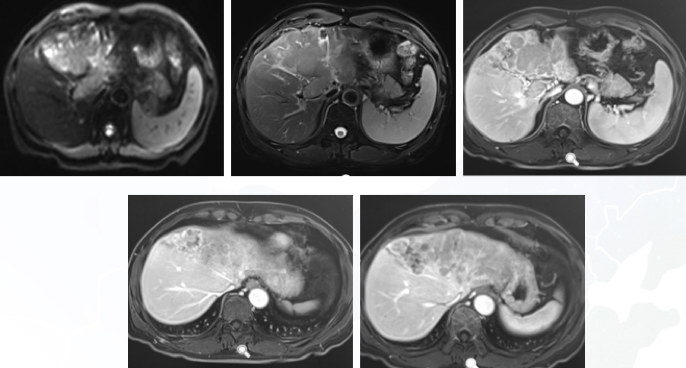

经MDT讨论,给予口服瑞戈非尼(2片/天)替代仑伐替尼方案,并联合经导管肝动脉灌注化疗(TACE)定期评估。2021年5月、7月、8月和11月均进行了MR复查,可见门脉癌栓至2021年8月无明显变化;2021年11月复查显示残肝右叶门静脉右支癌栓信号缩小(图4)。

图4. 2021年5月、7月、8月和11月MR复查

自2021年11月3日MR评估后,考虑疾病稳定,遂停用TACE,辅以PD-1抑制剂联合瑞戈非尼维持治疗半年;2022年5月我院MR未见明显改变。遂停用PD-1抑制剂,单纯使用瑞戈非尼,疗效待评估。